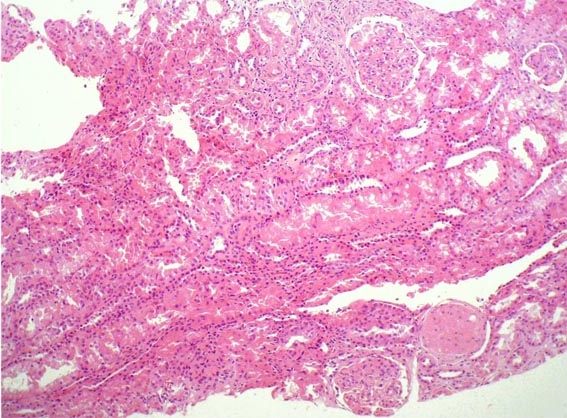

Observe las imágenes de esta

segunda biopsia.

Figura 1.

H&E, X100.